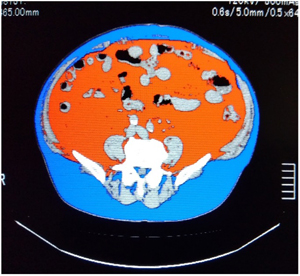

内臓脂肪CT

お臍の位置で画像を数枚撮影して、内臓脂肪と皮下脂肪の面積を測定します。生活習慣病のリスクが高まる内臓脂肪型肥満を判定できます。検査時間が短く撮影もお臍の位置の数枚だけなので被ばくも少ないです。

内臓脂肪が多いと心疾患や脳血管疾患が起こりやすくなります。内臓脂肪型肥満は隠れ肥満とも言われ痩せている人でも内臓に脂肪が蓄積し肥満となることがあります。

赤:内臓脂肪面積

青:皮下脂肪面積

内臓脂肪型肥満の方の画像になります。青の皮下脂肪に比べて赤の内臓脂肪面積の方が広いことがわかります。